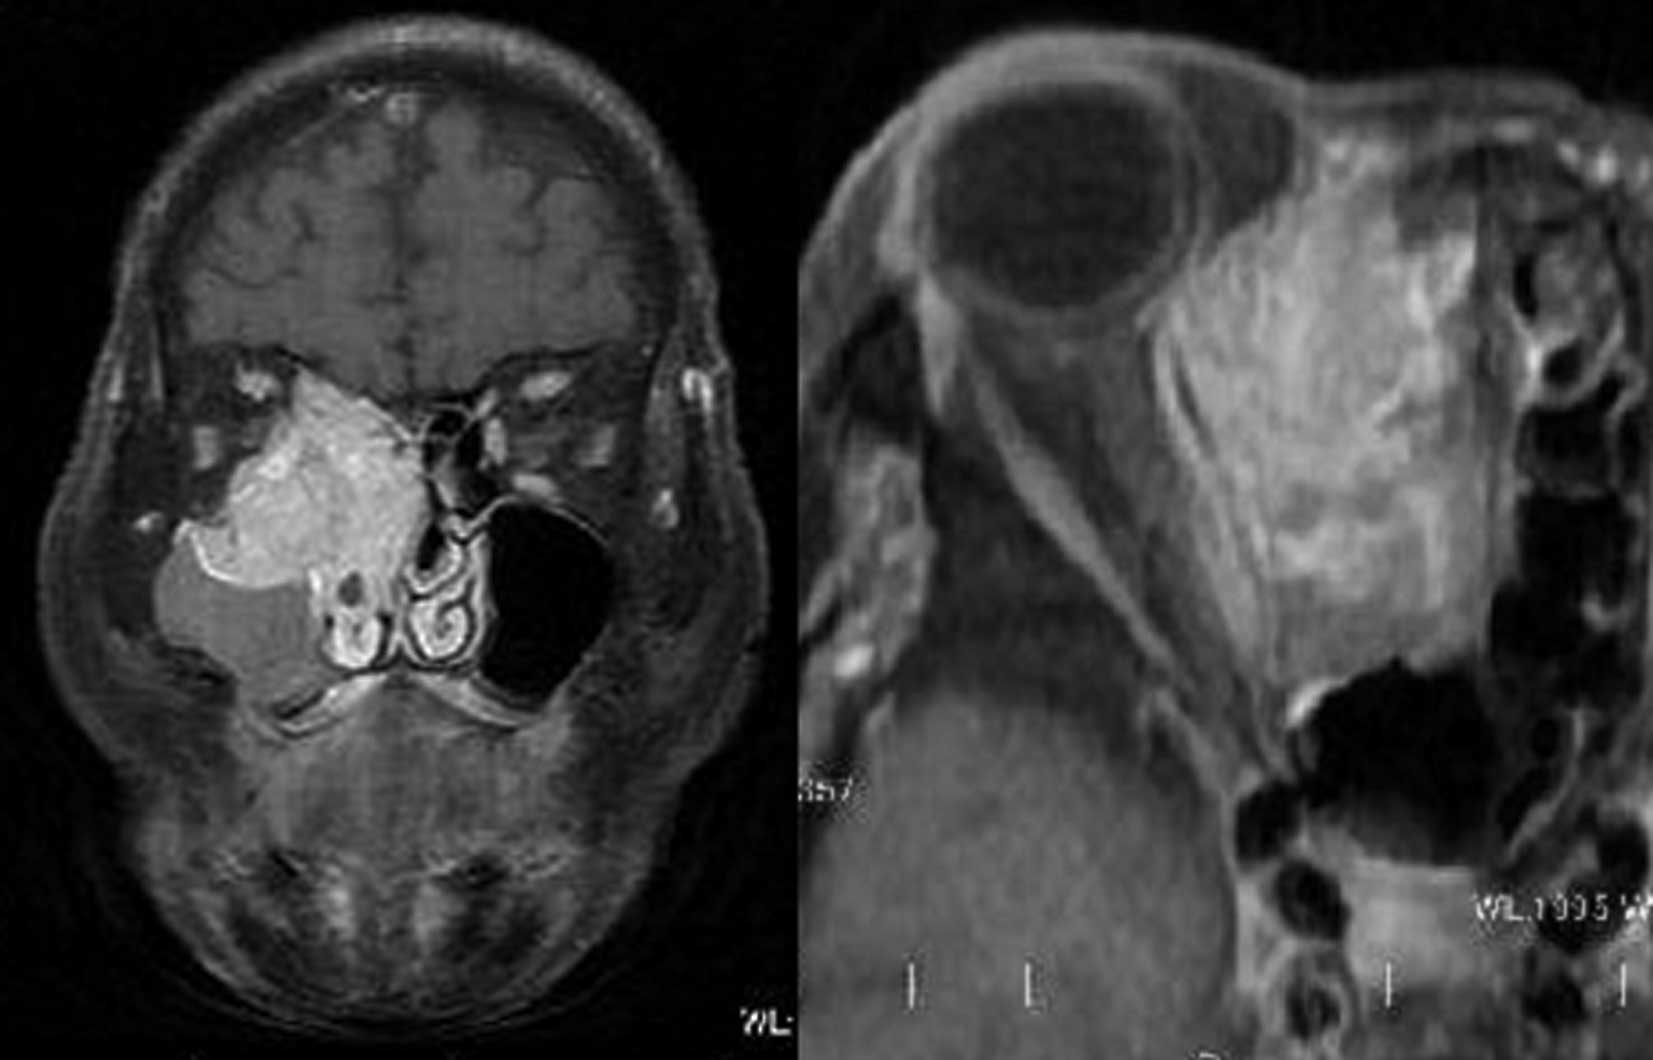

Esthésioneuroblastome

L’esthesioneuroblastome, également connu sous le nom de neuroblastome olfactif, est un cancer rare qui se manifeste dans le bulbe olfactive, la partie du cerveau qui interprète l’odeur. Les symptômes varient en fonction de l’emplacement et de l’étendue de la tumeur. Les symptômes les plus courants sont l’obstruction nasale, les saignements de nez, les maux de tête, les douleurs faciales et la diminution de l’odorat.

Les esthésioneuroblastomes sont traités chirurgicalement par chirurgie endoscopique endonasale et peuvent être suivis d’une radiothérapie ou d’une chimiothérapie.